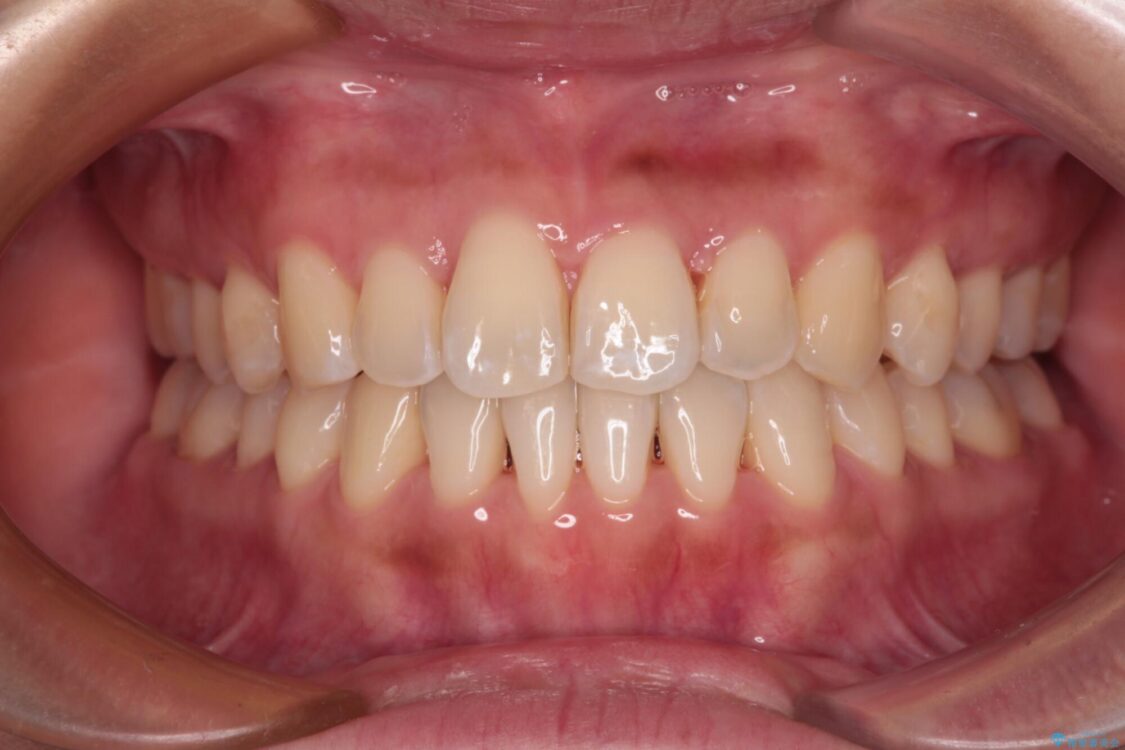

装着時間を守ってくださったので、予定通りの期間で終えることができました。インビザライン特有の、奥歯の咬み合わせの問題もなく、しっかりと歯列を改善することができました。

治療後

• 【モニター】前歯のデコボコをインビザラインで改善 治療後画像